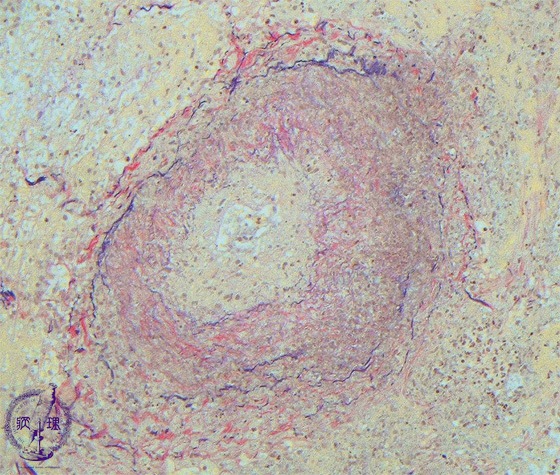

Microscopic view (intermediate power view; EVG staining): EVG stainingdemonstrates the residue of elastic fibers, suggesting necrotizing vasculitis.

Click the image to see the enlarged image.

• There is no guidance by arrows.